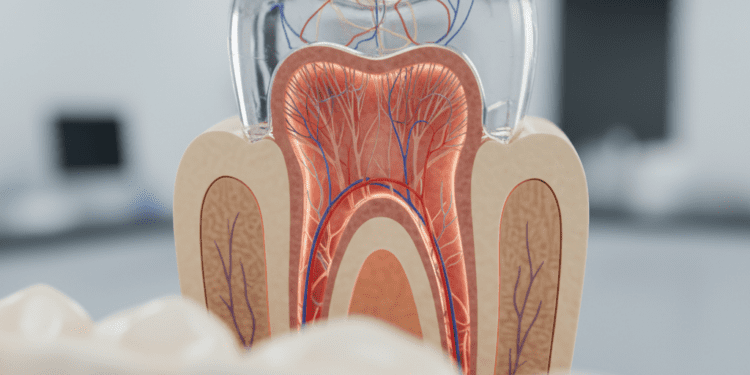

2. Dentina: O Coração do Dente

A dentina, localizada logo abaixo do esmalte, representa a maior parte da estrutura do dente. Essa camada é mais macia que o esmalte e contém túbulos microscópicos que se conectam à pulpa dental. A dentina é vital para a sensibilidade do dente, pois qualquer dano pode resultar em dor intensa.

Um aspecto interessante da dentina é que ela pode se regenerar em certa medida. Quando a dentina é danificada, o corpo pode produzir mais dentina em uma tentativa de proteger a polpa. Isso torna o cuidado preventivo ainda mais importante, pois danos prolongados podem levar a problemas mais graves, como infecções.

3. A Cavidade Pulpar: O Centro Nervoso

A cavidade pulpar é a parte interna do dente, onde se encontram os nervos e vasos sanguíneos. Essa estrutura é responsável pela nutrição do dente e pela percepção de dor. A polpa também desempenha um papel crucial na formação da dentina durante o desenvolvimento do dente.

Quando a pulpa é inflamada ou infectada, pode ser necessário realizar um tratamento de canal para salvar o dente. Os sinais de problemas na cavidade pulpar incluem dor intensa, inchaço e sensibilidade prolongada ao frio ou calor. A consulta ao dentista é essencial para diagnosticar e tratar adequadamente esses problemas.